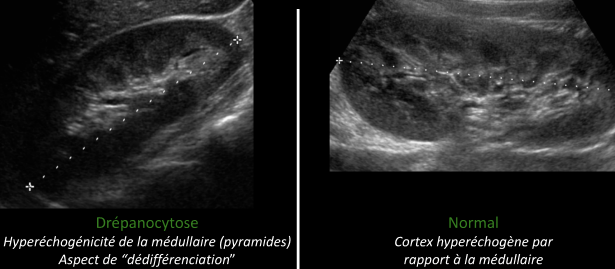

Reins

- Infarctus Rénaux dans la médullaire

- Dedifférenciation cortico médullaire à l’US

- Risque de Carcinome Medullaire (tumeur rare presque exclusivement trouvée chez les Drepa)